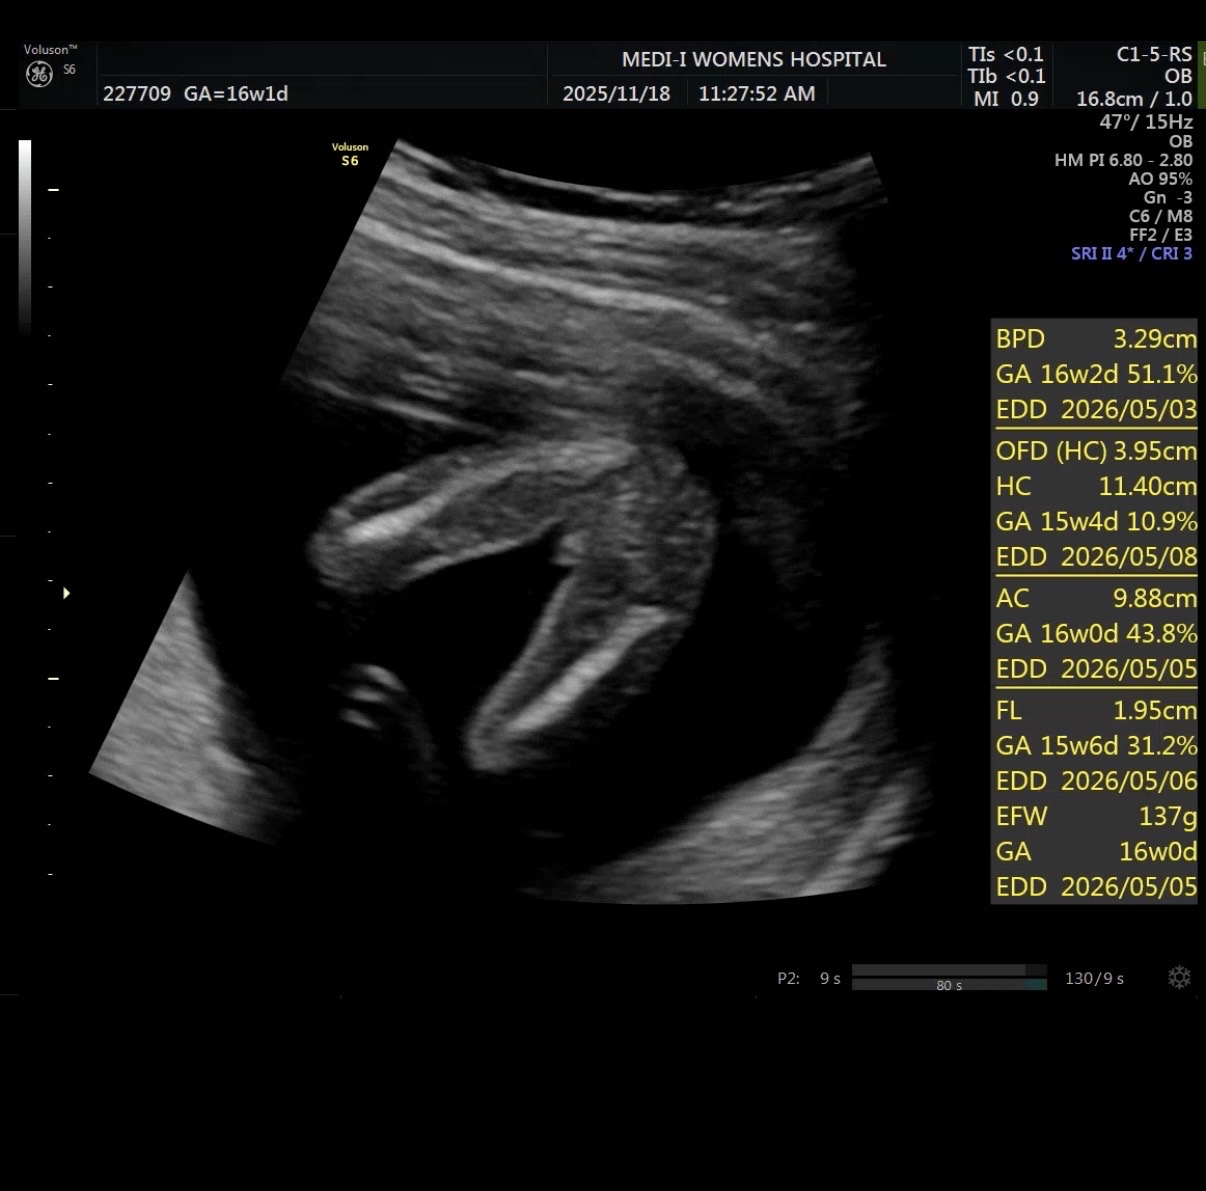

16주차 성별 봐주세요 ~~!

16주차로 초음파 했는데 딸 70%라고는 했는데 존 계속 가운데가 아들같아서요🥹 혹시 한번봐주세요~~~!

탯줄? 일수도?! 저도 남안줄 알았는데 탯줄이였더라구요🤣